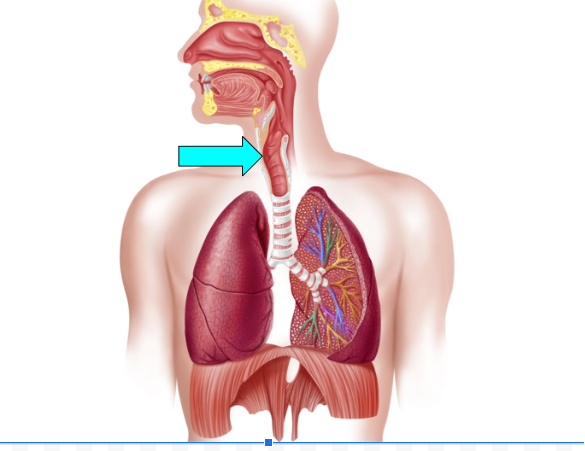

Larynx (pic)

Larynx

facilitates breathing, creates vocal sounds, & prevents food/foreign particles from entering the airway